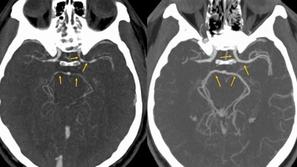

Zožitev arterij

Čili: Po zaužitju popularne zelenjave so ga odpeljali na urgenco

Računalniška tomografija glave pokazala, da so se moškemu močno zožile arterije.